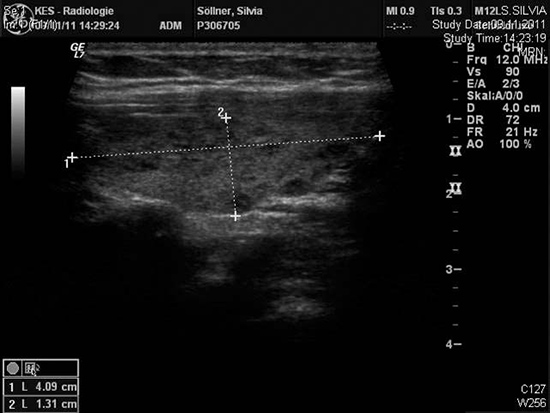

Die Ursache ist oft eine unerkannt ablaufende Schilddrüsenentzündung (Thyreoiditis Hashimoto). Das Immunsystem des Körpers greift die Schilddrüsenzellen an und stört die Funktion in unterschiedlichem Ausmaß, langfristig kommt es zu einer Unterfunktion, die mit Hormonersatztherapie behandelt wird. Manchmal verschwindet die Schilddrüse nahezu gänzlich ("atrophe" Form). Die Abwehrzellen (Lymphocyten) besiedeln das Organ und können im Ultraschall ein "fleckiges" Muster erzeugen. Mitunter treten auch Knotenbildungen auf, man nennt das dann "hypertrophe" Form der Thyreoiditis Hasimoto. Eine komplette Schilddrüsendiagnostik ist erforderlich, vor allem um auszuschließen, dass eine unter den Knoten eine maskierte Krebserkrankung übersehen wird.

| Ultraschall mit typischem Hasimoto Bild |